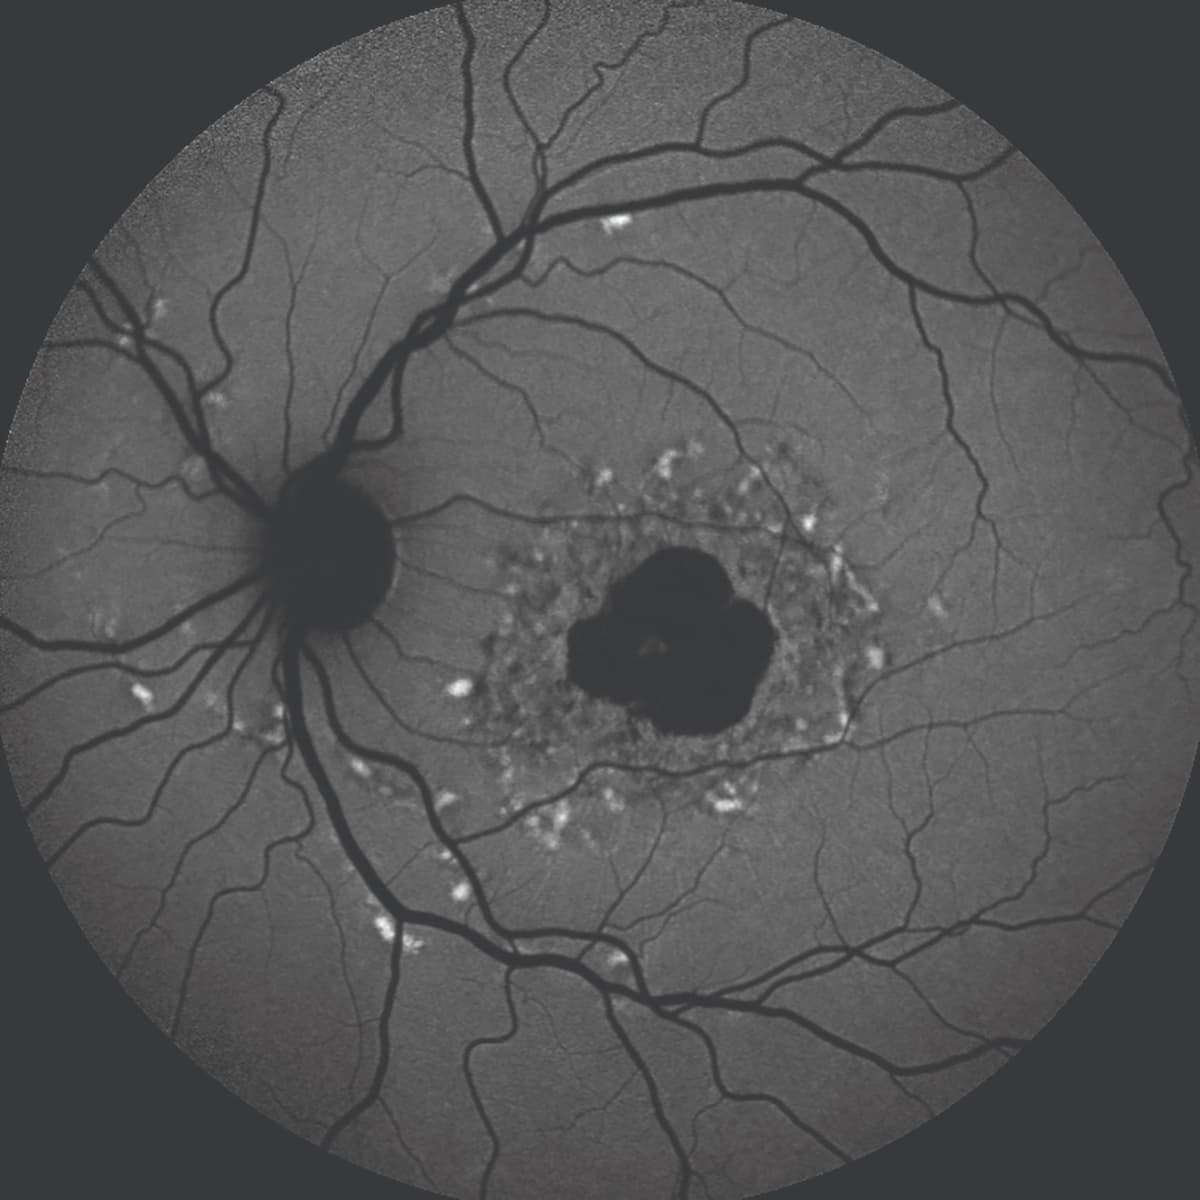

Figure 2 (bottom): A blue fundus autofluorescence image of a patient with Stargardt disease. Note (1) the elongated pisciform deposits, which are hyperautofluorescent, and (2) the intensely deep hypoautofluorescence due to the accumulation of lipofuscin within the retinal pigment epithelium cells.

Fluorescein angiography (FA) is a useful tool for differentiating IRDs from GA, which can look similar in some cases. Stargardt disease is one of the more common of these. The condition often begins in childhood or adolescence, but its characteristic fundus appearance of flecks and localized atrophy can sometimes be mistaken for GA in older patients. Stargardt disease can be identified by “choroidal silence” or a very dark choroid that is visible on FA (along with irregular deposits), which is due to lipofuscin masking choroidal fluorescence (Figure 2).